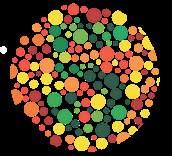

має форму двоввігнутого диска (мал. 9.3), що збільшує площу поверхні для газообміну порівняно з кулястою формою. Еритроцити гнучкі, тож можуть протискуватися вузькими капілярами. У людини, як і у всіх ссавців, еритроцити є без’ядерними. Еритроцити заповнені молекулами гемоглобіну білка, який містить гем із катіоном Fe2+, що

Аглютиногени системи

у таблиці 2.

Якщо, наприклад,

ві А (ІІ), то на

аглютиноген А, а в

нін β. Переливання їй донорської крові групи В (еритроцити містять аглютиноген В) призведе до злипання еритроцитів, оскільки аглютині-

ни β плазми реципієнта зв’язують аглютиноген В як чужорідний агент.

Таким чином, для успішного переливання донорська кров має містити такі самі аглютиногени, як і

еритроцитів білка, який називається резус-фактор. Якщо в людини еритроцити мають резус-фактор, то вона резус-позитивна, якщо не мають резус-негативна. Резус-фактор також обов’язково враховується під час переливання крові, бо імунна система резус-негативних людей реагує на резус-позитивну кров як на чужорідну. Запитання